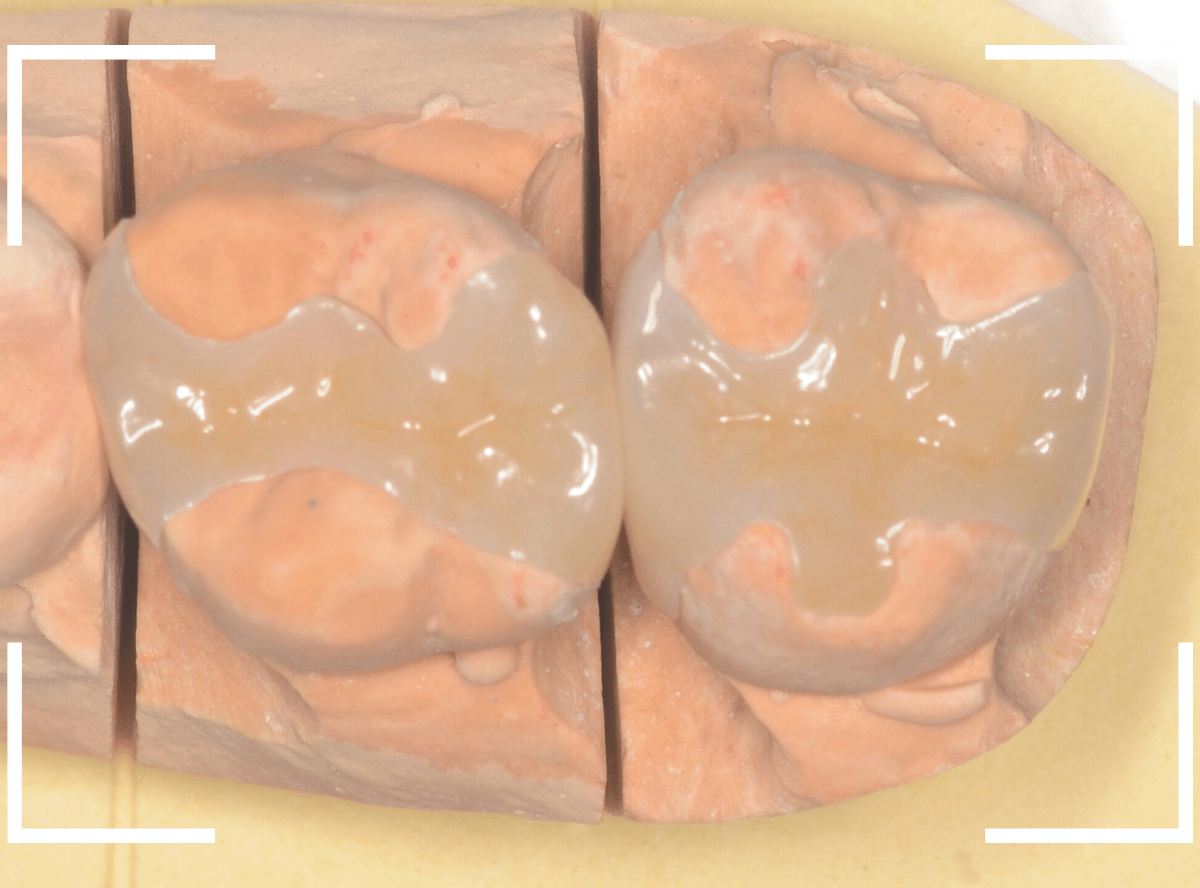

Case.16 2歯連続、E-MAXインレー修復のケース

隣接面(隣の歯とのすき間)の大きな虫歯の治療をされた患者さんです。

隣接面が広く虫歯になった際は、レジンよりもつめもの(インレー)処置をした方が、長く持たせられる事が多いです。

今回は、白い歯をご希望されましたので、E-MAXインレーでの治療となりました。

隣接面が広い虫歯の場合、なぜ、レジンよりもインレーの方が長く持たせられるのか。

その一つは、虫歯や歯周病の好発部位ではる隣接面は特に精密に歯の形を作る必要があります。

その為には、お口の中で歯の形を製作するレジンよりも、型をとって模型上で隣接面を再現するつめ物の方が精密度が高くなる事が多いためです。

こちらが、型をとって製作した模型です。

分割模型といって、矢印の部分で模型を外せる仕様になっています。

細かい歯の形態を手元でしっかり確認して製作できるわけです。

暗く操作性の悪いお口の中での処置よりも、精密度は高くなりますよね。

最終的なつめ物(E-MAX・インレー)をsetしたところです。

上から見ても、側面から見ても、患者さんに満足していただける仕上がりになりました。